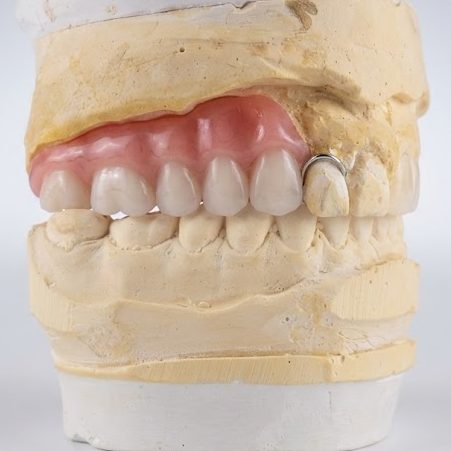

We help you restore

confidence and comfort to your patients through exceptional removable prosthetics.

Welcome to Innovative Dental Lab, our focus is quality in fabricating your removable appliances such as:

Full Dentures – Esthetic, balanced, and functional.

Partials – Seamless fit with superior retention.